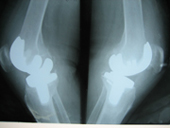

Arthritis both knees varus deformity pre op Post op Total Knee Replacement Post op Total Knee Replacement